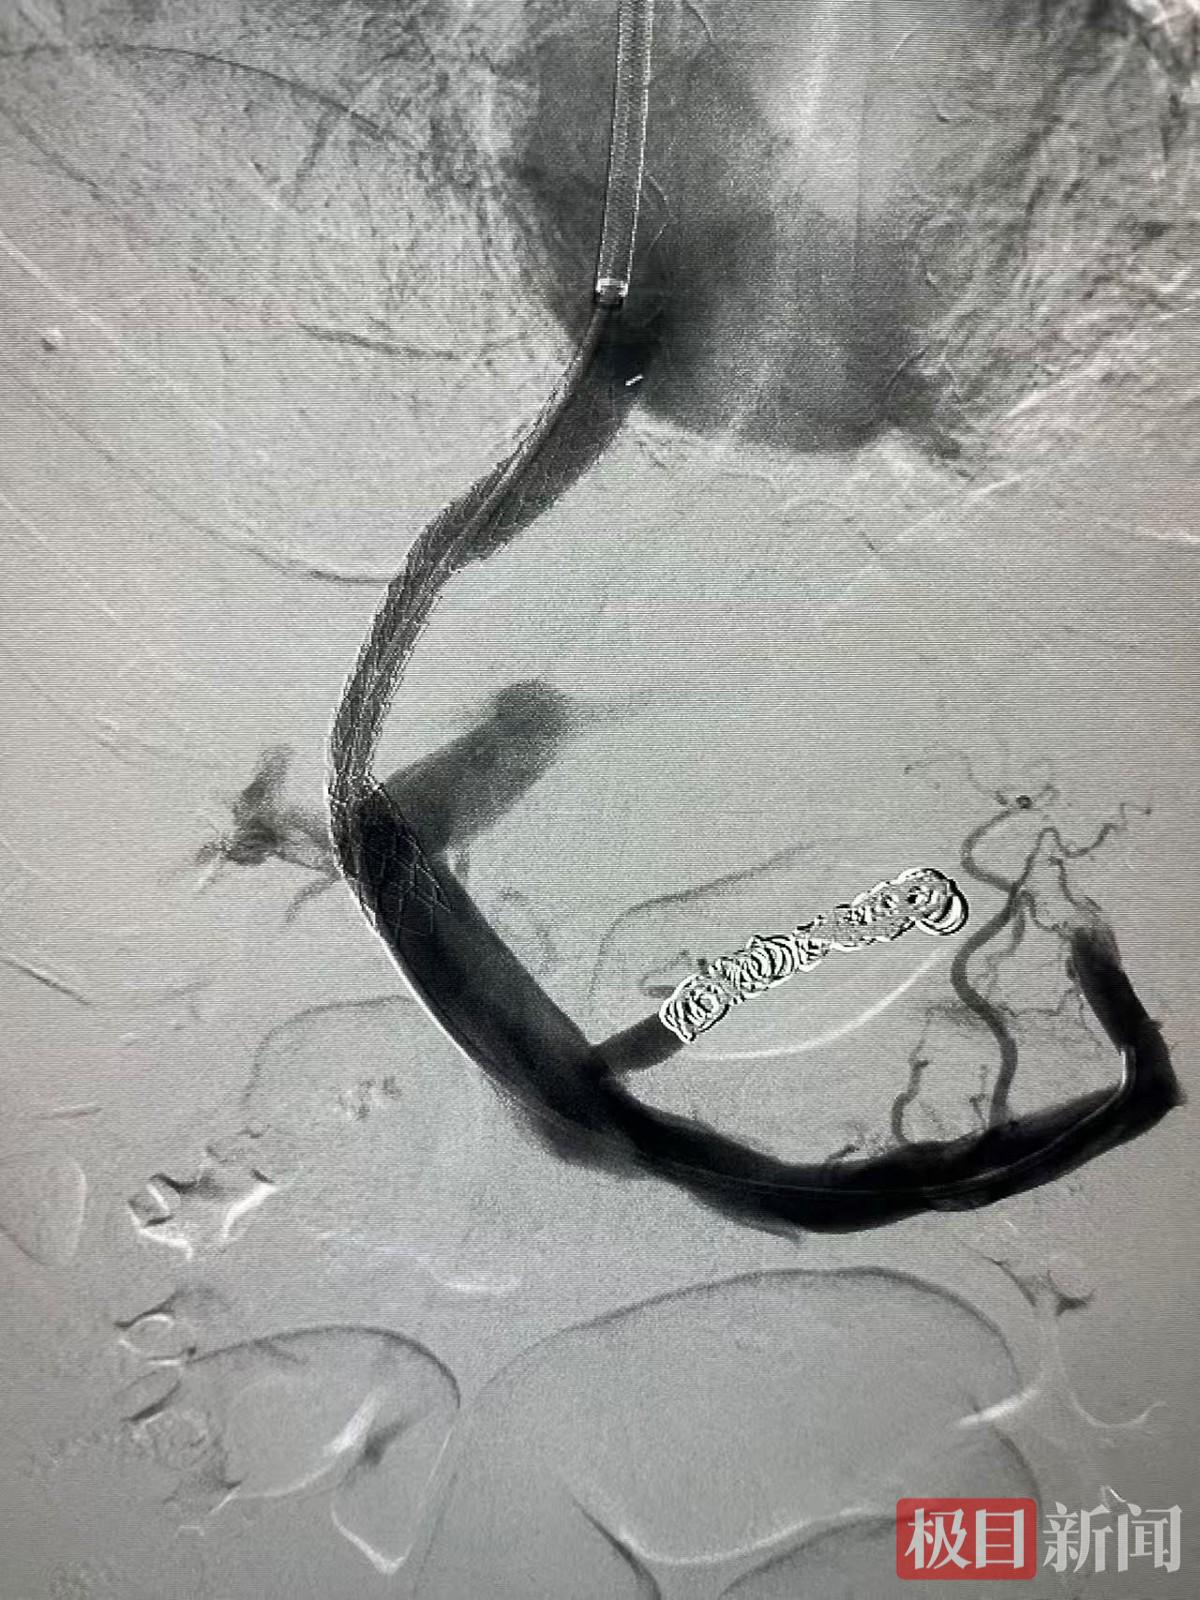

月初,高先生经过一系列治疗后生命体征平稳,手术如期进行。在血管造影系统DSA设备引导下,专家们犹如在肝脏内部进行精密的“管道施工”,通过颈静脉这个微小入口,在患者的肝内建立了一条连接门静脉与肝静脉的“分流隧道”,并植入支架。术中造影显示,术后门静脉压力下降,严重曲张的胃底静脉也随之萎缩。术后,高先生的大便颜色恢复正常,精神状态好转,顽固的腹水也得到了控制。

术后门静脉压力下降,严重曲张的胃底静脉也随之萎缩